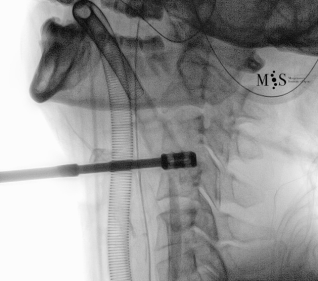

Imágenes de una cirugía de fusión cervical endoscópica

Animación de la inserción de una caja intersomática por vía endoscópica percutánea.

Nótese la apertura (expansión) de la pared posterior del disco al insertar la caja.